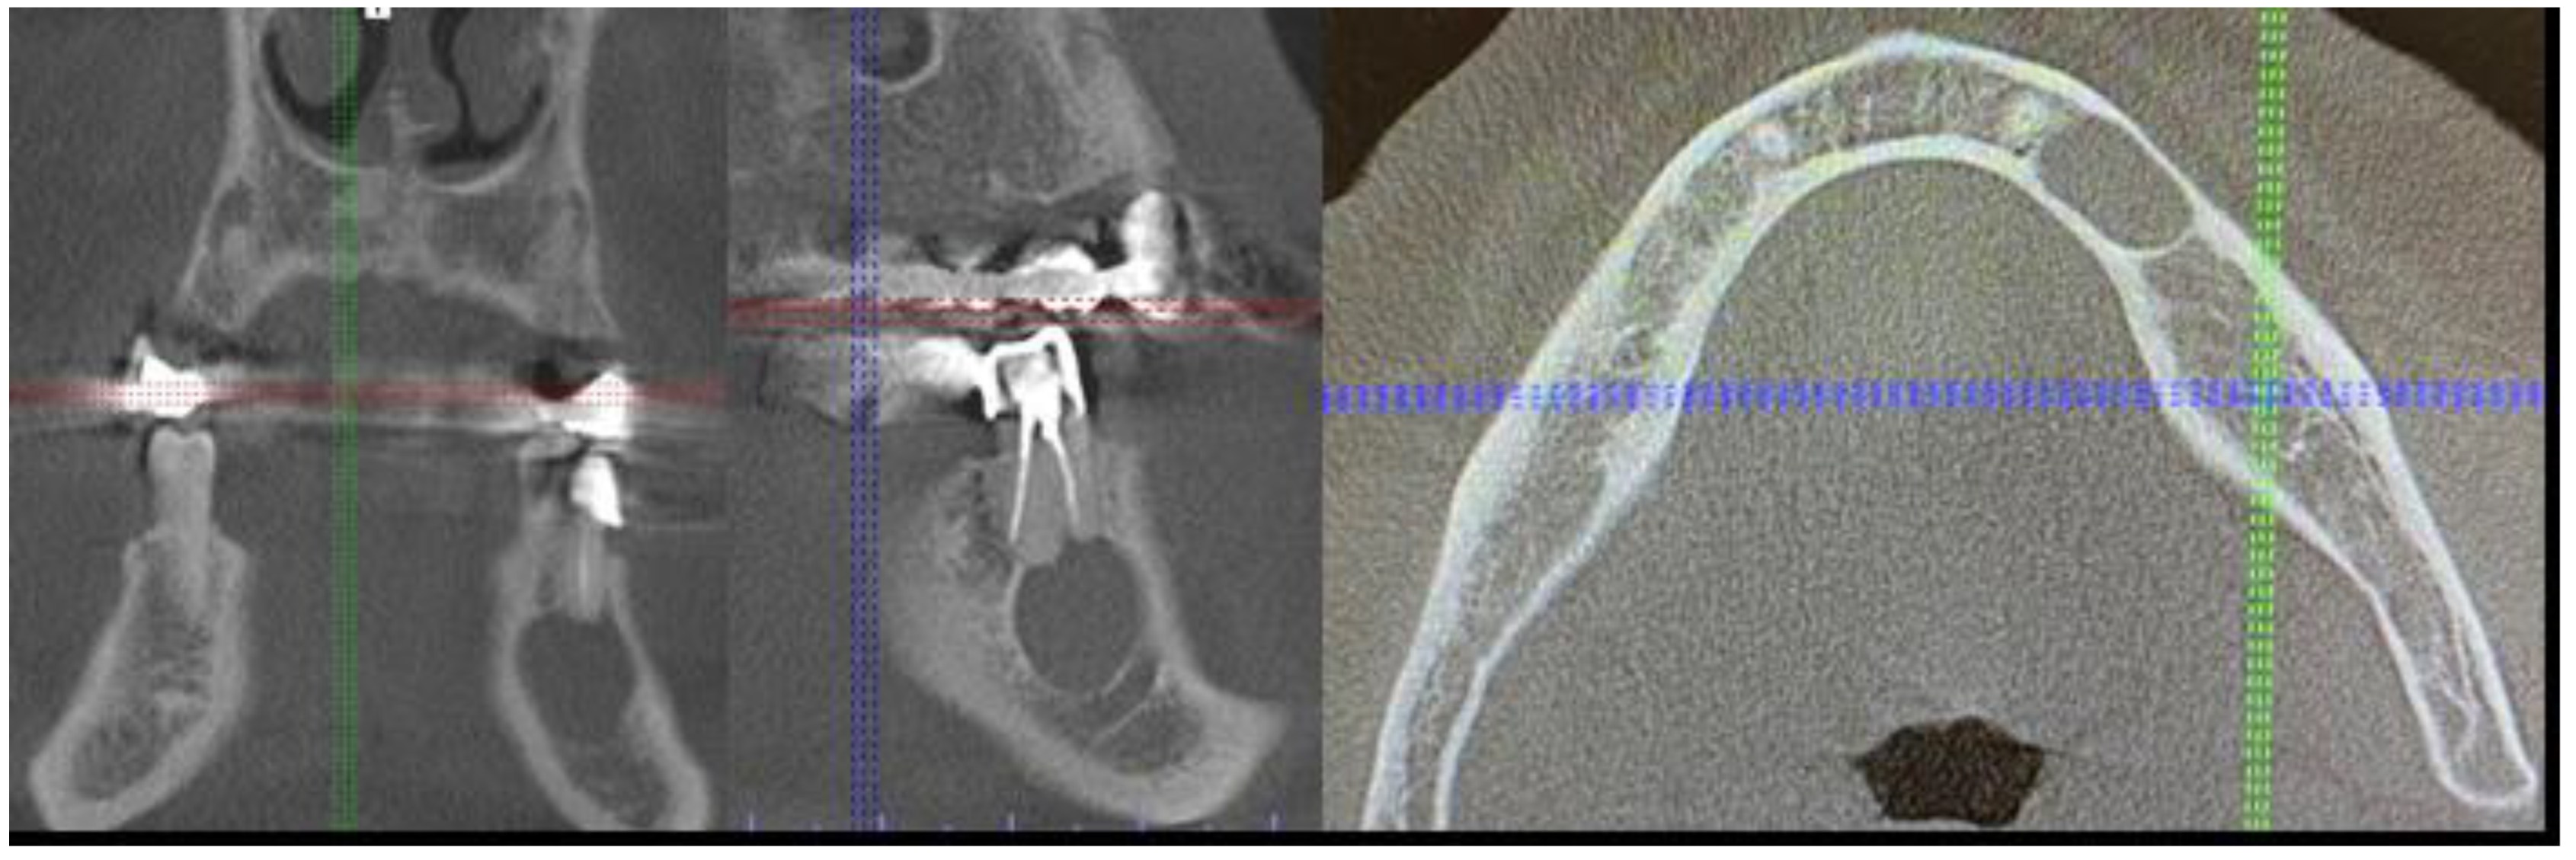

2. Case Description

- A close CBCT evaluation before surgery;